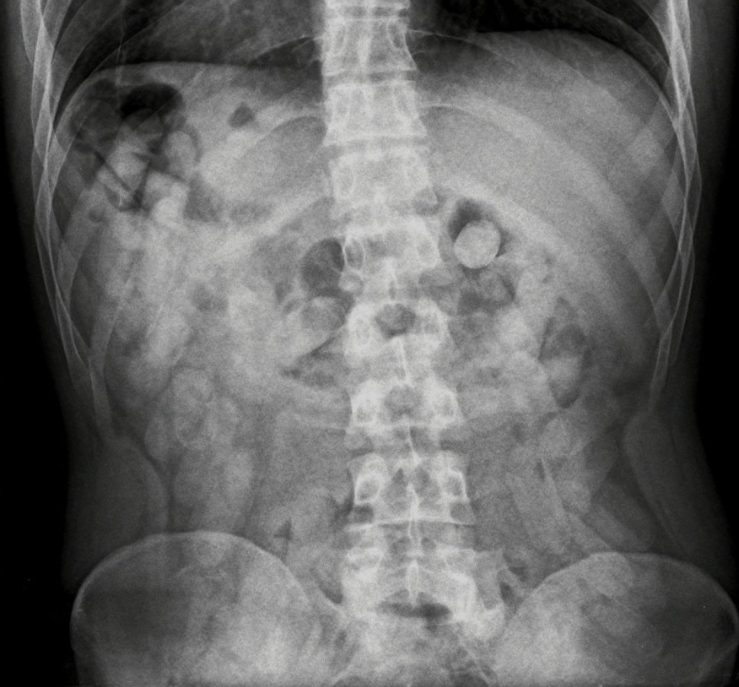

Durante la inspección, cuatro pasajeros de nacionalidad boliviana, debido a fuertes dolores estomacales, manifestaron haber ingerido dosis de drogas. Entendiendo que la modalidad “mulas” o “capsuleros” es altamente peligrosa para la salud, se trasladó a los involucrados al Centro de Salud Zenón J. Santillán ubicado en la ciudad de Tucumán, donde les realizaron las placas radiográficas y pudieron observar la presencia de cuerpos extraños en la zona del abdomen.